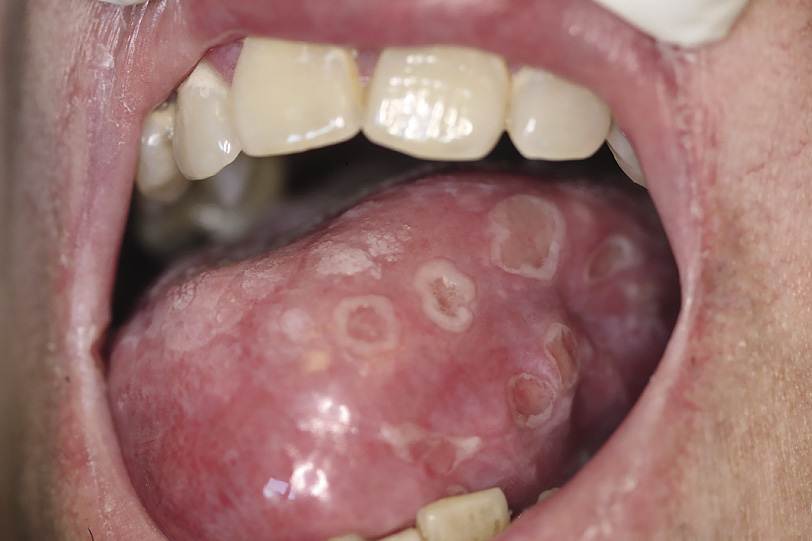

- оболочка слизистой в ротовой полости приобретает ярко-красный цвет и отек, а в области щек, губ, языка и небного дужка образуются высыпания пузырьков мелкого размера, примерно с просяное зерно. Обычно пузырьки располагаются в одну группу.

- пузырьки вначале заполняются прозрачным веществом, но потом начинают мутнеть, а через двое или трое суток лопаются, образуются множество одиночных или обширных эрозий ярко-красного цвета. Эти эрозии довольно скоро покрываются желтым фибринозным или белесоватым налетом.

- многочисленные афты, покрытые налетом белесоватого цвета, которые образовались после вскрытия пузырьков герпетических.